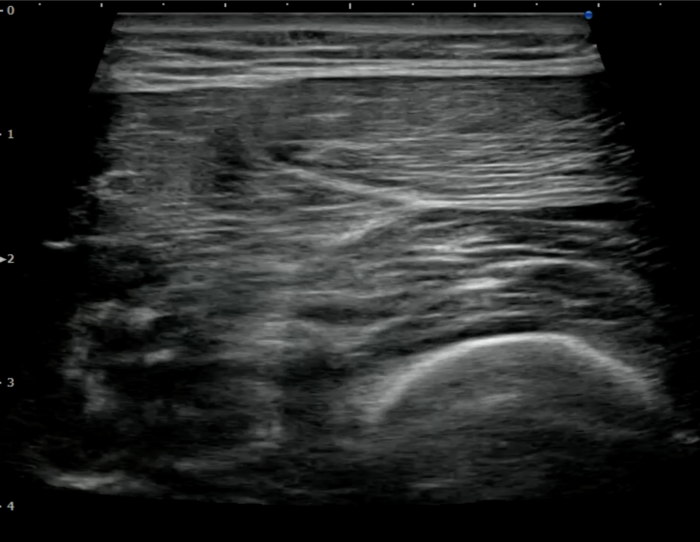

① エコーで血腫の大きさ・深さを確認できる

モモカンは、見た目だけでは重症度が分かりません。

エコー検査を使うと、

•浅い血腫か?

•深い血腫か?(←重症化しやすい)

•筋肉の断裂があるか?

を正確に判断できます。